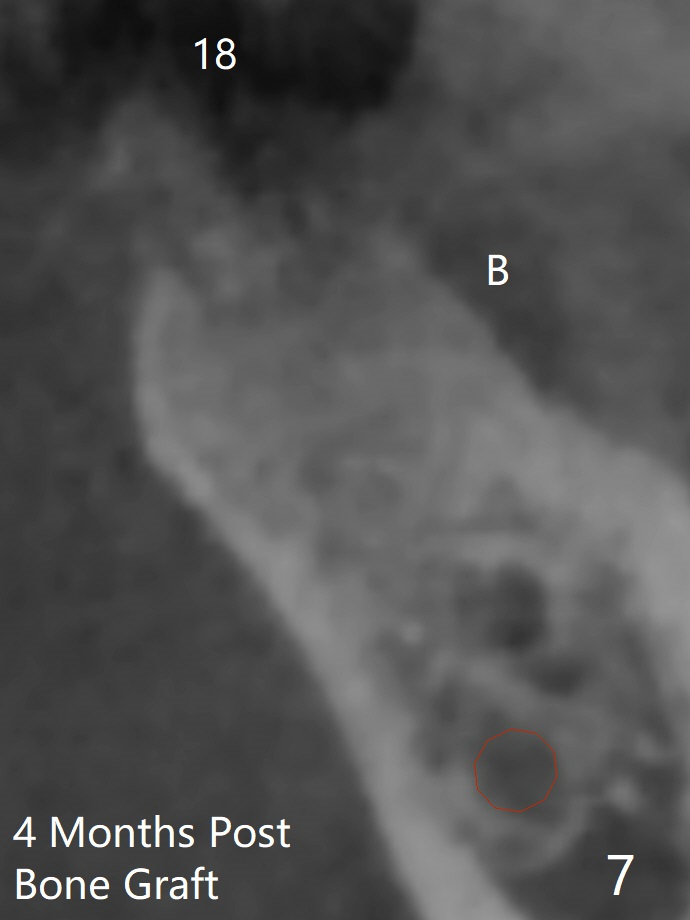

Bone Density Post Extraction with or without Bone Graft

16 Months Post Graft